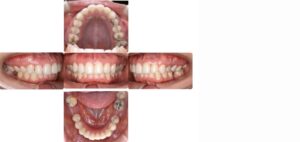

29歳の女性の患者さん。

「前歯が出ている、虫歯が原因で奥歯を2本失った」というお悩みで来院されました。

下顎左右の奥歯が失われた状態でしたが矯正治療でスペースを閉じて、上の歯は左右の小臼歯を抜歯して矯正用のアンカースクリューを併用して上の前歯を後ろに下げる治療を行いました。

結果、前歯の出っ張りが改善し自然に口を閉じられるようになり奥歯でしっかり噛める様になりました。(装置はハーフリンガル)

矯正治療前

矯正治療後

※【診断】下顎左右第一大臼歯欠損を伴う上下顎前突【治療期間】約3年2ヶ月